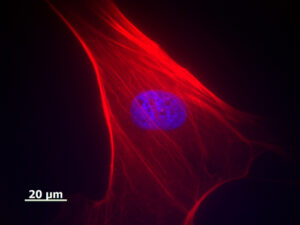

Scienziati finlandesi, tedeschi e canadesi hanno identificato anormalità genetiche associate alla riprogrammazione di cellule adulte in cellule staminali pluripotenti indotte...